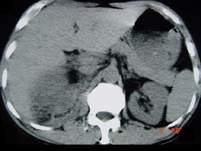

问题 男,25岁,右腰部疼痛伴血尿,有外伤史,CT扫描如图所示,应诊断为 ( )

选项 A、右肾梗死 B、右肾脓肿 C、右肾血管平滑肌瘤 D、右肾癌 E、右肾挫伤并包膜下血肿

答案 E